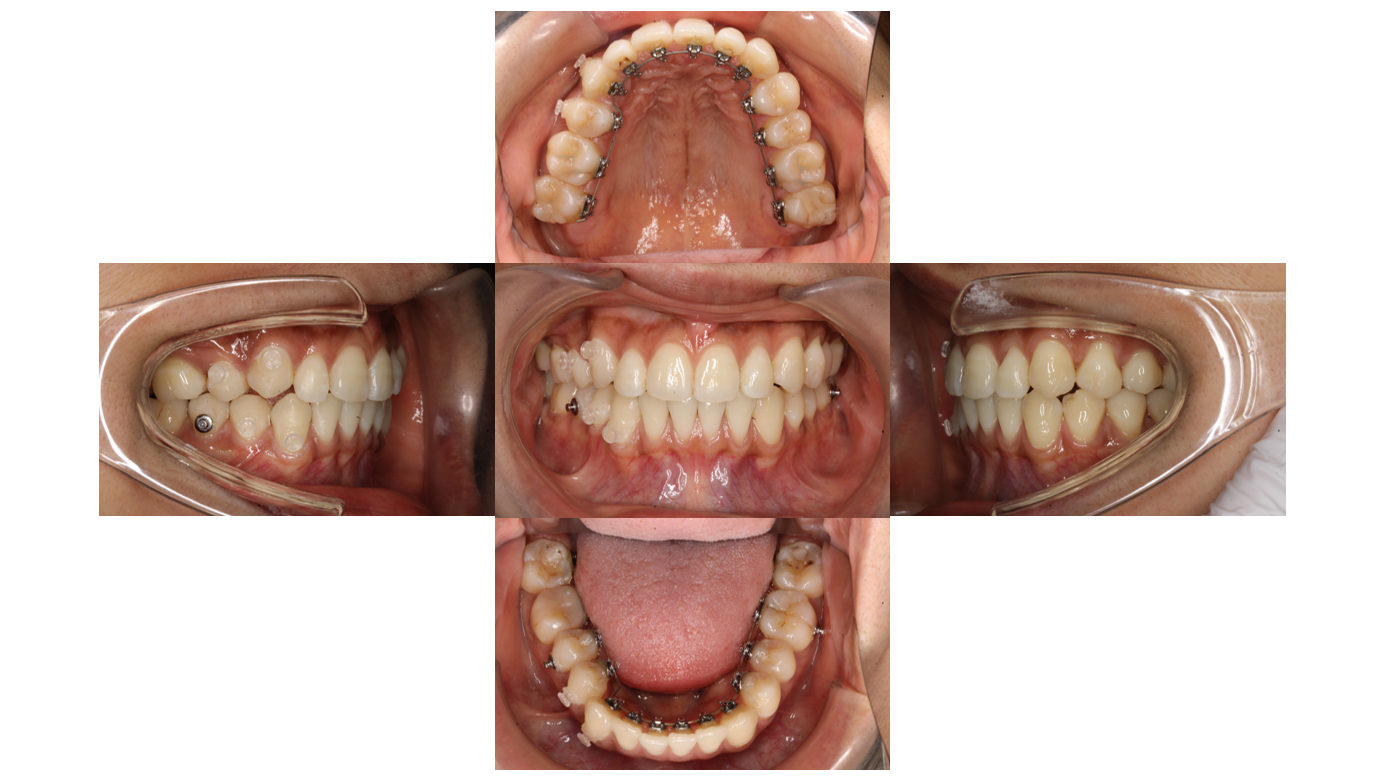

装置装着後

上下とも裏側に矯正装置が付きました

上の青い材料は下の歯と装置が当たらないようにつけています